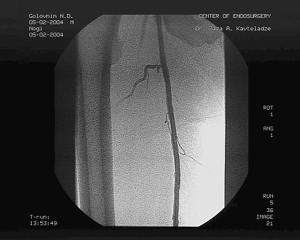

Пациенту произведена баллонная ангиопластика и стентирование правой ОПА и ОБА, реканализация обеих ПБА с последующей баллонной ангиопластикой и стентированием через подколенные пункционные доступы с обеих сторон. Баллонная ангиопластика ОПА и ОБА проводилась баллонами диаметром 10 и 7мм с последующим стентированием, диаметр и длина стентов 10 мм и 60 мм в ОПА, 8 мм и 40 мм в ОБА, соответственно. Реканализация ПБА проведена с обеих сторон гидрофильным проводником "Road Runner" с последующей баллонной ангиопластикой баллонами диаметром 6 и 7 мм и стентированием. Во всех артериях установлены ZA-стенты соответствующего диаметра и длиной от 40 до 80 мм. Всего установлено 6 стентов: в правую ОПА, правую ОБА, правую ПБА, 3 стента в левую ПБА: 1 в проксимальной части, начиная от устья , 2 в зоне Гунтерова канала. (см. рис. 3)

Рис. 3. Контрольная ангиография после реканализации и стентирования левой ПБА.